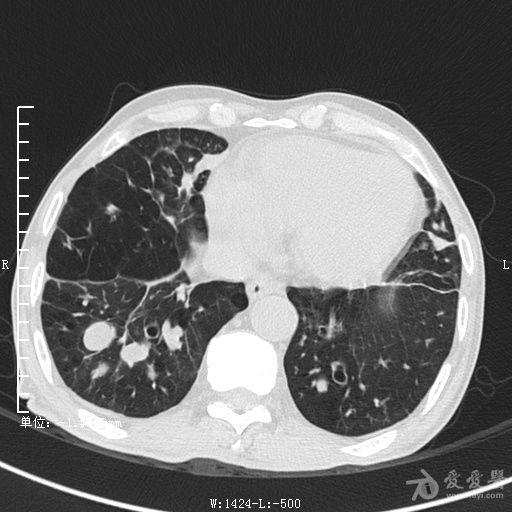

典型支气管扩张及肺水肿CT片

典型支气管扩张肺水肿